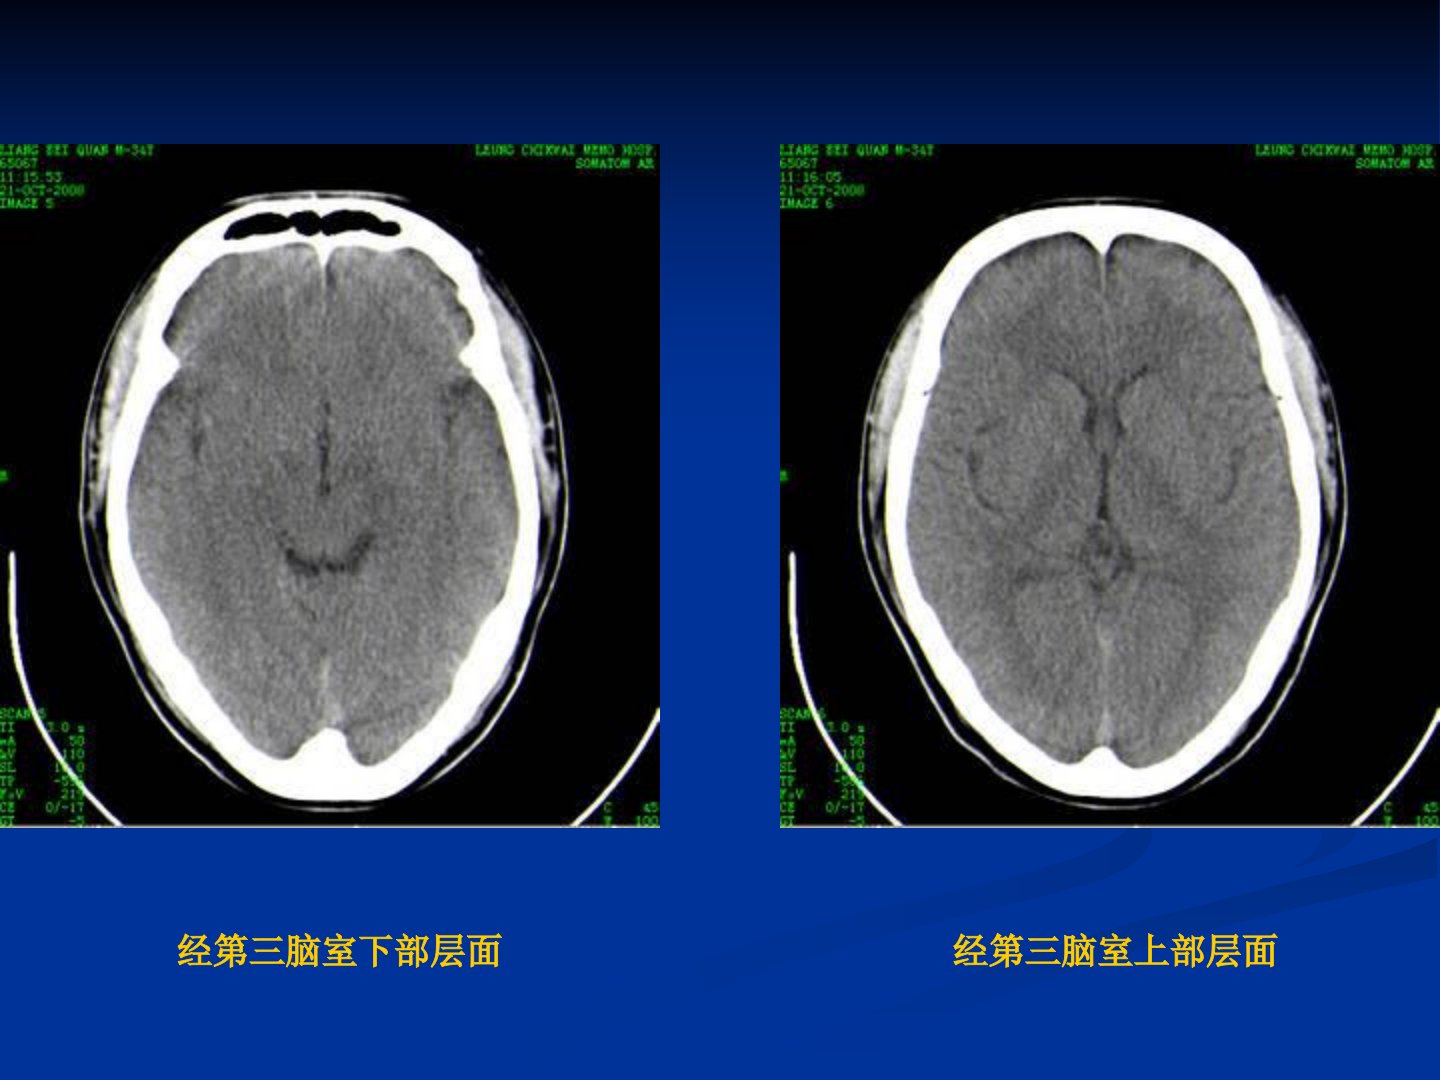

颅脑CT征象及外伤疾病CT诊断摘要本文介绍了颅脑基本解剖包括大、小脑半球颅骨脑动、静脉与脑膜等结构。随后阐述了颅脑病变的基本CT征象:1密度:CT以物质密度为基础成像高密度如出血、钙化灶表现为更白区域低密度如水肿灶表现为更黑区域。2占位效应:颅内占位性病变或组织肿胀会造成中线结构移位、脑室受压等严重导致脑疝。负占位效应则表现为陈旧性软化灶等对周围组织的牵拉移位。3脑萎缩:分为局灶性和弥漫性CT可见脑回变细、脑沟增宽等。4脑水肿:包括血管性、细胞毒性和间质性CT表现为病灶密度减低、组织肿胀。5增强检查:可提高组织对比度发现微小病变了解病变血供特点对病变定性有重要意义。6伪影:包括移动伪影、高对比伪影、射线硬化伪影等。7部分容积效应:定位时需多层面观察薄层扫描可减少其影响。最后介绍了颅脑外伤性疾病包括硬膜下血肿与硬膜外血肿的鉴别及CT诊断价值。